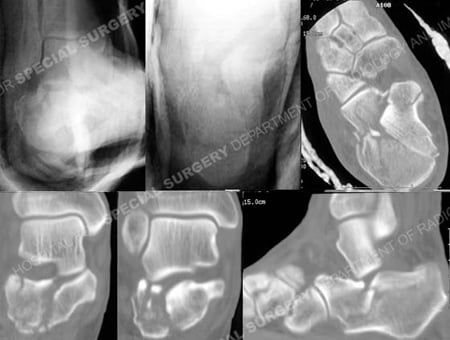

Plain radiographs and CT scan images of the right foot revealing a right-sided calcaneus fracture.